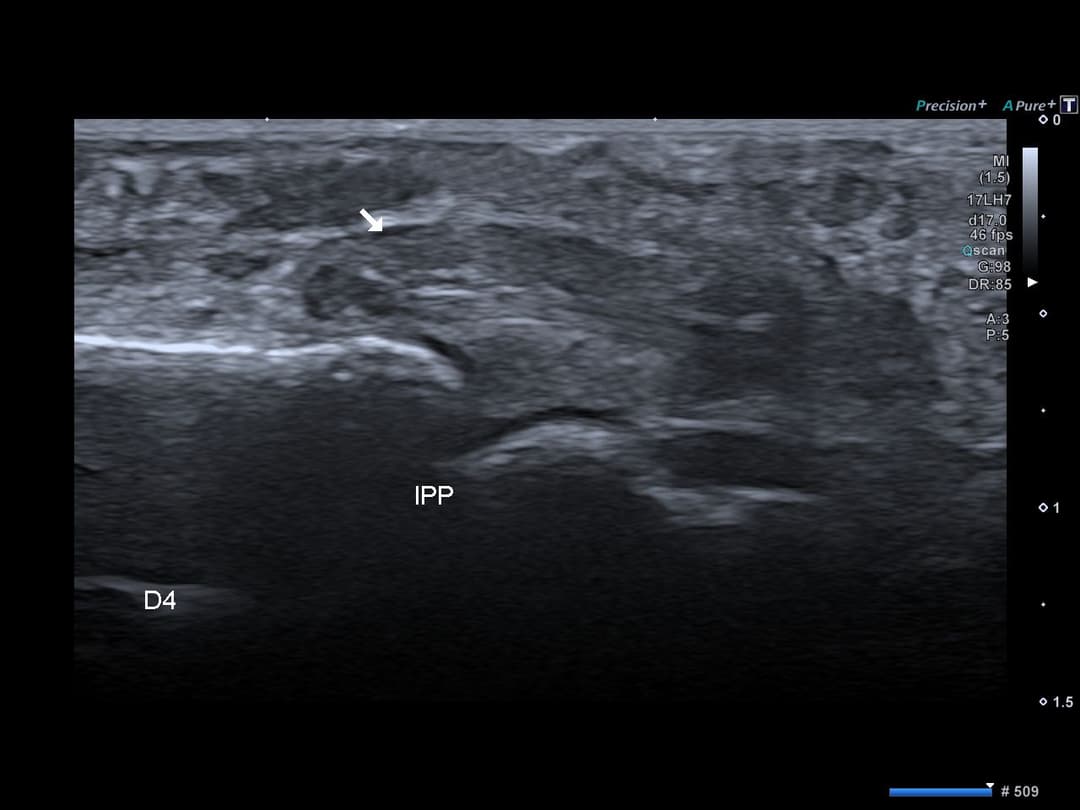

Échographie

Rétraction du moignon proximal en regard de l'articulation interphalangienne proximale (type 2 de la classification de Leddy et Packer).

Ecart interfragmentaire évaluée à 2.3 cm

Type II : Le tendon est rétracté jusqu'au niveau de l'articulation interphalangienne proximale (IPP).